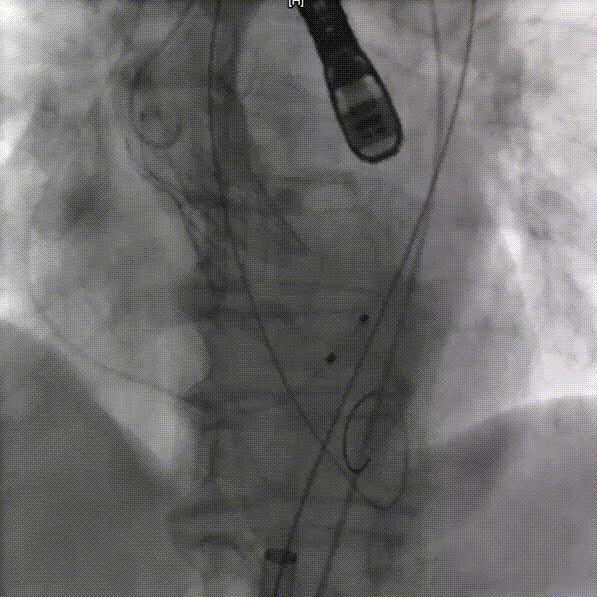

右侧主入路造影

左侧辅入路造影

主动脉根部造影